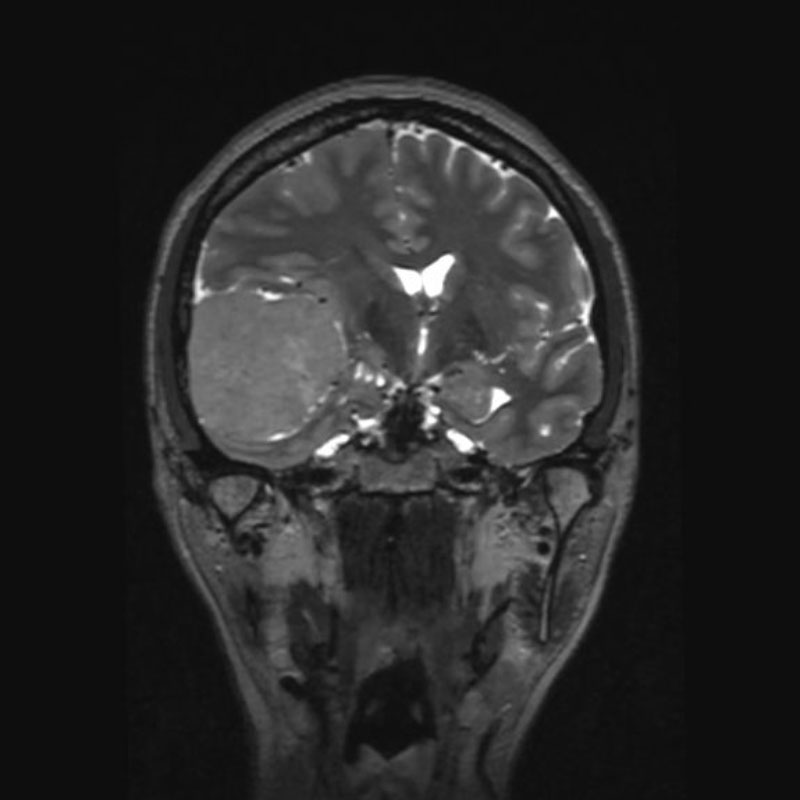

右聴神経腫瘍

頭蓋内腫瘍摘出術

No.’25_28 手術前1

No.’25_28 手術前2